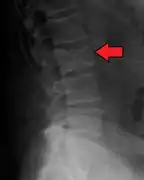

The diagnostic examination of a person with suspected multiple myeloma typically includes a skeletal survey. This is a series of X-rays of the skull, axial skeleton, and proximal long bones. Myeloma activity sometimes appears as "lytic lesions" (with local disappearance of normal bone due to resorption). And on the skull X-ray as "punched-out lesions" (raindrop skull). Lesions may also be sclerotic, which is seen as radiodense.[52] Overall, the radiodensity of myeloma is between −30 and 120 Hounsfield units (HU).[53] Magnetic resonance imaging is more sensitive than simple X-rays in the detection of lytic lesions, and may supersede a skeletal survey, especially when vertebral disease is suspected. Occasionally, a CT scan is performed to measure the size of soft-tissue plasmacytomas. Bone scans are typically not of any additional value in the workup of people with myeloma (no new bone formation; lytic lesions not well visualized on bone scan).

X-ray of the forearm, with lytic lesions

Pathological fracture of the lumbar spine due to multiple myeloma